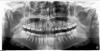

Force Опубликовано 5 октября, 2011 Поделиться Опубликовано 5 октября, 2011 Удаление 18 28 38 48. Снятие брекетов. Кондилография. Анализ окклюзии в артикуляторе. Определение терапевтической позиции на шине. Стабилизация челюсти. Лечение на вестибулярной брекет-системе на многопетлевой технике (MEAW). Такова тактика ведения пациентов с дисфункцией ВНЧС (что у вас в полном объеме, судя по стертым головкам сустава). Ссылка на комментарий

Makeit Опубликовано 5 октября, 2011 Автор Поделиться Опубликовано 5 октября, 2011 Сложно со слов комментировать, только после непосредственного осмотра и диагностики можно с уверенностью сказать, что происходит не так... Мне совсем не понятно, например, для чего и как там 8-ки перемещают?Тактика была выбрана такая: просто переместить верхний зубной ряд до совмещения центральной оси с нижним зубным рядом, т.к мне было сказано что моя проблема кроется именно в зубах а не в челюсти (что тоже предпологалось, но после ортопантомограммы, почиму-то,исключилось). Вот, и начали сдвигать по одному зубу начиная с 18 назад. Ссылка на комментарий

Skip Опубликовано 5 октября, 2011 Поделиться Опубликовано 5 октября, 2011 Тактика была выбрана такая: просто переместить верхний зубной ряд до совмещения центральной оси с нижним зубным рядом, т.к мне было сказано что моя проблема кроется именно в зубах а не в челюсти (что тоже предпологалось, но после ортопантомограммы, почиму-то,исключилось). Вот, и начали сдвигать по одному зубу начиная с 18 назад. По ОПТГ тех нарушений, о которых я говорил, не определить, только в артикуляторе, причём можно в мм вычислить, сколько на уровне зубов, а сколько на краниальном уровне. Ссылка на комментарий

Makeit Опубликовано 5 октября, 2011 Автор Поделиться Опубликовано 5 октября, 2011 По ОПТГ тех нарушений, о которых я говорил, не определить, только в артикуляторе, причём можно в мм вычислить, сколько на уровне зубов, а сколько на краниальном уровне.Но вы же как-то предположили что у меня именно то что вы сказали?По моей ОПТГ даже я заметила что у меня с верхней челюстью каки-то проблемы, и как мне показалось, не связанные с зубами. Ссылка на комментарий

Skip Опубликовано 5 октября, 2011 Поделиться Опубликовано 5 октября, 2011 Но вы же как-то предположили что у меня именно то что вы сказали? По моей ОПТГ даже я заметила что у меня с верхней челюстью каки-то проблемы, и как мне показалось, не связанные с зубами. Да я тоже заметил на ОПТГ , хотя использую для этого специфическую, более достоверную диагностику, да и 10 лет практики, в этом направлении, сказывается Ссылка на комментарий